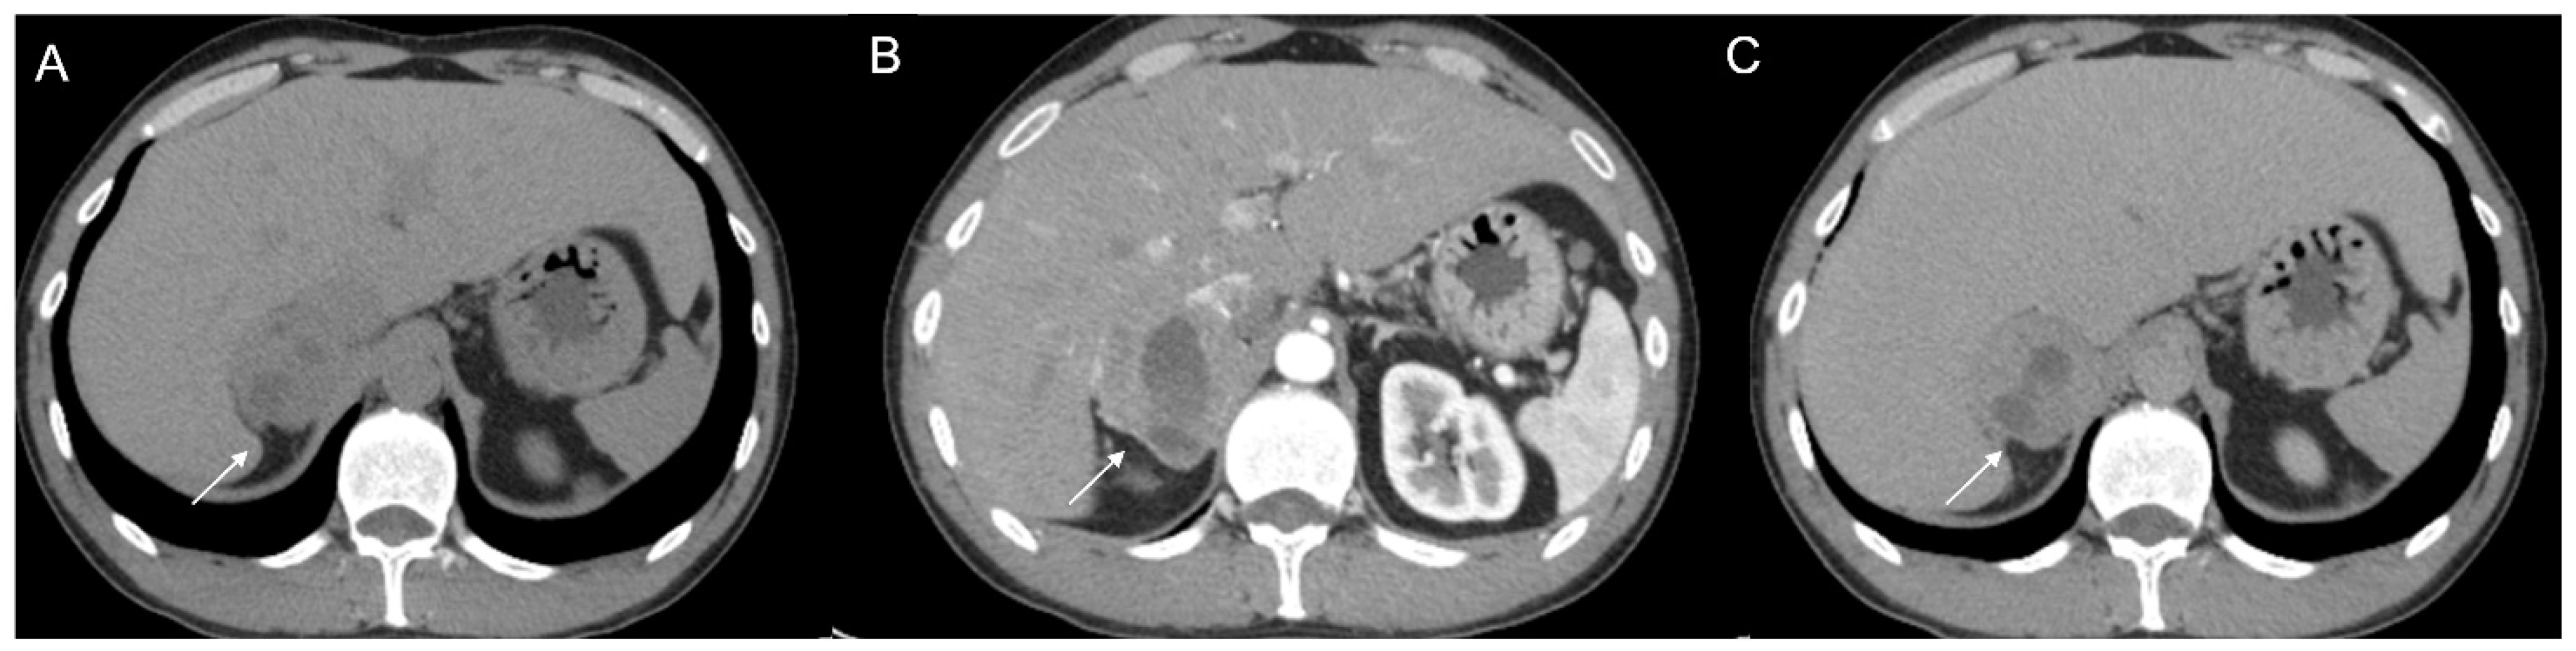

Figure 8.

79-year-old female patient with left adrenal lesion detected at abdominal ultrasound performed for abdominal pain. Homogeneous left adrenal mass with density on non-contrast CT (A) less than 10 HU (6 HU, SD4 HU) and washout (>60%) in the venous (B) and late post-contrast phases (C), compatible with adenoma.